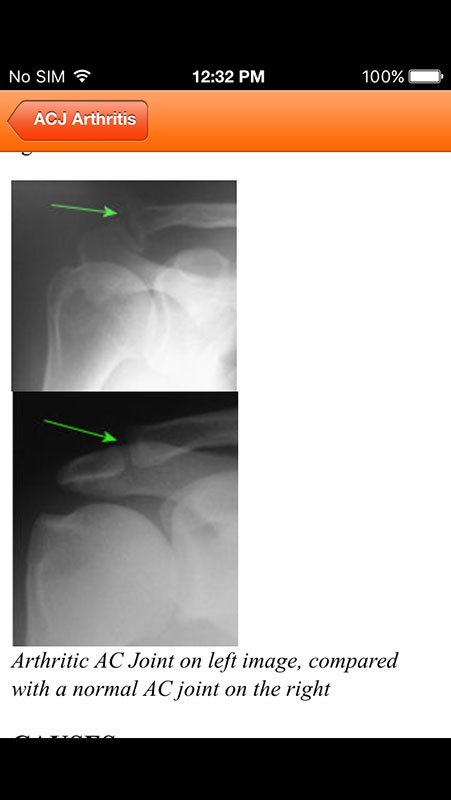

Information on each shoulder condition is comprehensive and well-referenced, and it's provided in a form of text, accompanied by annotated anatomy illustrations, photos, radiographs, and animations to help illustrate the condition.

The information contains a summary of the problem and common treatment options, which is tailored to be easily comprehended by patients without medical training.